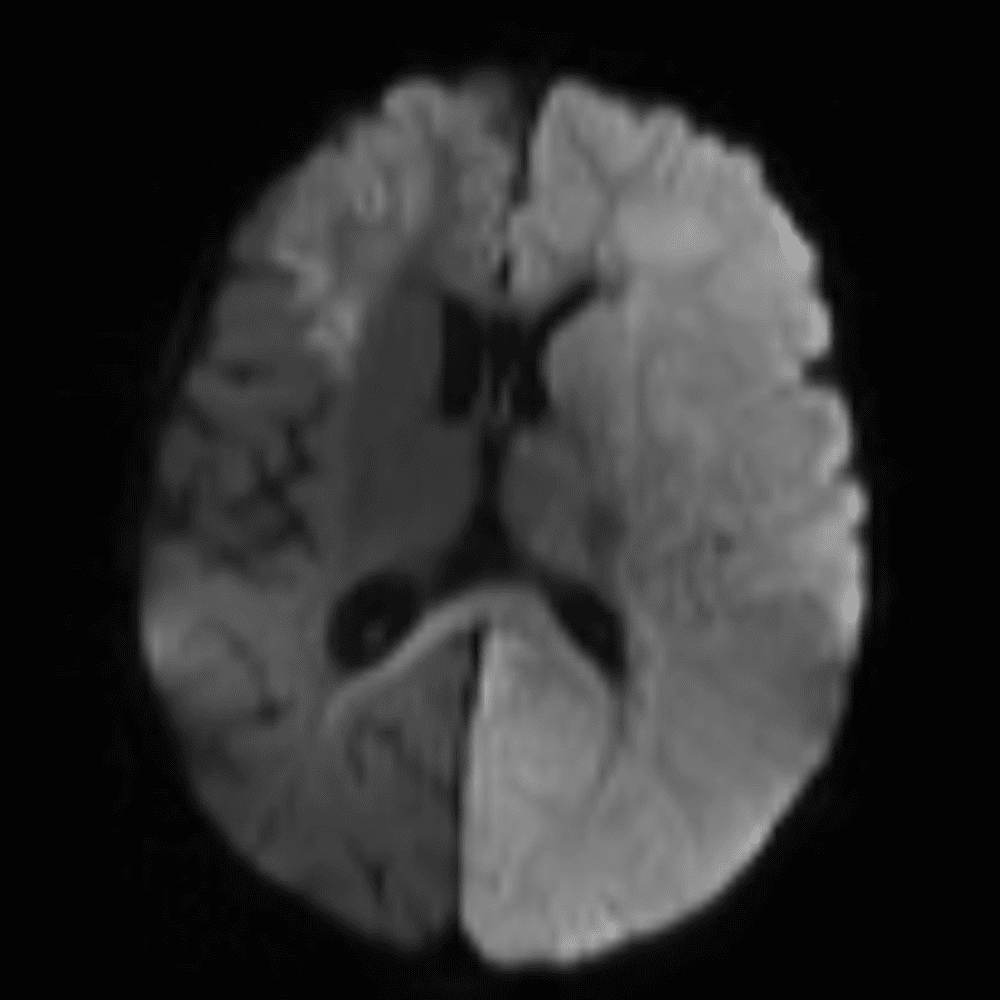

๋‹น์ง ์‹œ ํ”ํžˆ ๋ณผ ์ˆ˜ ์žˆ๋Š” ์‚ฌ๋ก€์˜ ์ „ํ˜•์ ์ธ ์˜ˆ๋ฅผ ํฌํ•จํ•ฉ๋‹ˆ๋‹ค.

39 ์‚ฌ๋ก€

์—ฐ์Šต

๋ฏธ๋ฌ˜ํ•˜๊ฑฐ๋‚˜ ์–ด๋ ค์šด ์‚ฌ๋ก€์™€ ์ผ๋ถ€ ์ •์ƒ ์‚ฌ๋ก€๋ฅผ ํฌํ•จํ•˜์—ฌ ๋‹น์ง์„ ์‹œ๋ฎฌ๋ ˆ์ด์…˜ํ•ฉ๋‹ˆ๋‹ค.

50 ์‚ฌ๋ก€